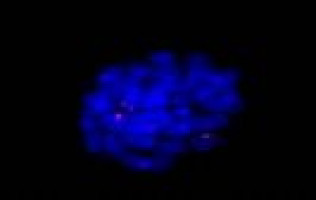

In chronic myeloid leukaemia, the hematopoietic stem cell undergoes a genetic mutation by recombining chromosome 9 and 22.

As a result, gene building blocks fuse that would otherwise not be in contact with each other.

The incorrectly assembled chromosome is called Philadelphia chromosome and harbors the construction manual for the so-called BCR-ABL oncogene.